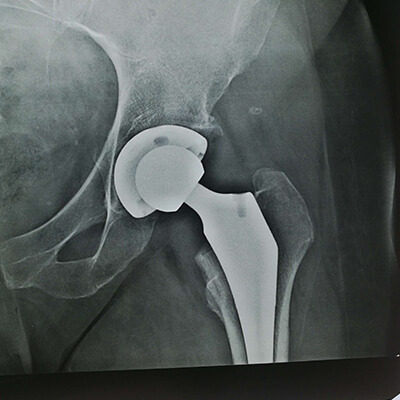

В своей практике использую прогрессивную малоинвазивную методику замены тазобедренного сустава передним доступом Бикини, которая имеет ряд неоспоримых преимуществ перед стандартным протезированием.

Пациент выписывается из клиники на 2-3 день, не имеет массивного повреждения тканей, быстро возвращается к нормальной жизни, болевой синдром после операции значительно меньше.